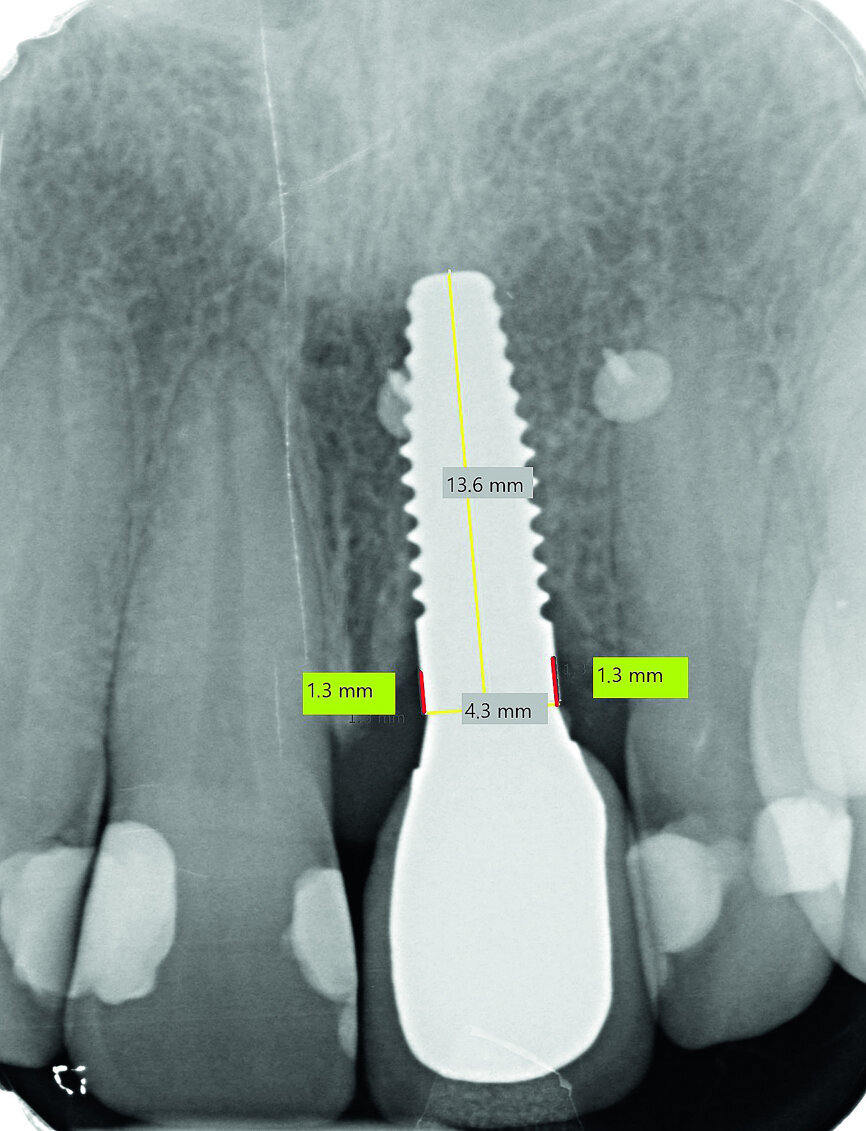

Fig. 13a: Bone resorption was detected after six months and bone gain after 12 months. The yellow line represents the actual implant length (13.6mm). The red lines indicate the mesial and distal distances from the top of the implant to the first bone contact.

Fig. 13b: Bone resorption was detected after six months and bone gain after 12 months. The yellow line represents the actual implant length (13.6mm). The red lines indicate the mesial and distal distances from the top of the implant to the first bone contact.

Fig. 13c: Bone resorption was detected after six months and bone gain after 12 months. The yellow line represents the actual implant length (13.6mm). The red lines indicate the mesial and distal distances from the top of the implant to the first bone contact.

Bone resorption was detected six months after exposure (mesial bone: 0.6 mm; distal bone: 0.4 mm), and a gain of bone was observed 12 months after exposure (mesial bone: 0.0 mm; distal bone: 0.3 mm; Figs. 13a–c). In accordance with the findings in the relevant literature, bone resorption in our patient was the greatest in the first six months.16 However, the literature findings are in reference to one-piece ceramic implants, in contrast to the two-piece implant system used in this case. This phenomenon of bone resorption is a relatively rare occurrence in implantology and should be confirmed by evidence-based long-term studies before a definitive conclusion can be drawn. Evaluations are in progress.